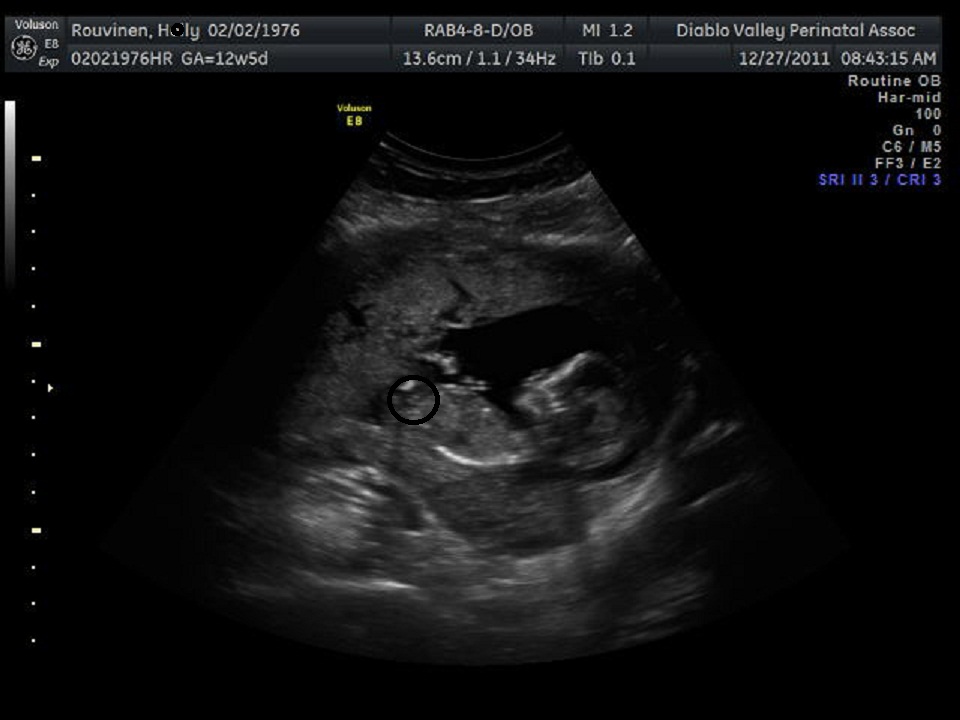

Added another shot just of the skull...what do you think?

Attachment 1043

Nub looks like a fork, fork can go either way. Scull looks boyish.